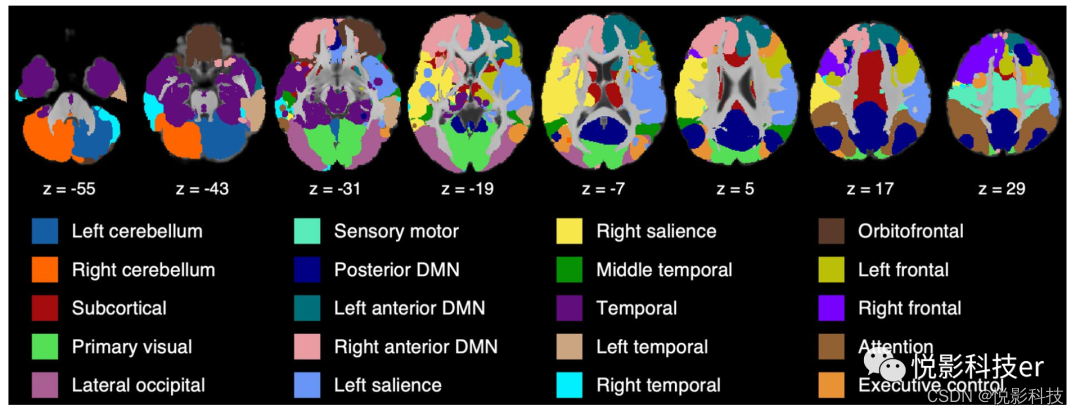

3.2 静息态功能脑图集

谱聚类算法从rs-fMRI数据中识别出22个功能网络。图5a展示了轮廓系数,表明轮廓系数在大脑被分为22个功能网络时达到最大值。目测舍弃2个主要位于脑白质和脑脊液的功能网络,得到最后20个功能网络。图4展示了大脑轴向图上的20个功能网络,图6提供了每个网络的三视图。20种功能网络的描述信息如表S2所示。

图4 静息态功能图集

小脑和皮下网络。小脑被分为左小脑和右小脑两个功能网络,而皮层下网络包括基底神经节、丘脑和中扣带。图6的第一排显示了两个小脑网络和一个皮层下网络。

初级感觉皮层。20功能网络包括3个主要感觉网络,即位于运动皮层的感觉运动网络、位于楔叶的初级视觉网络和枕侧网络(图6中第二排)。

DMN和显著网络。默认模式区域被划分为三个功能网络(图6中的第四行)。楔前叶、扣带回后和角回组成了后默认模式网络(DMN)。内侧额叶、前扣带和尾状核进一步聚集到左、右前DMN中。同样地,脑岛、壳核和丘脑被分成两个单侧功能网络,即左显著和右显著(图6中第三排的前两个面板)。

颞叶网络。颞叶被划分为四个功能网络。中颞网络位于中颞区(图6第6行第1个图),颞网络覆盖了颞极、海马、旁海马和杏仁核(图6中5行第1个图)。两种网络均呈现双侧模式。将下颞和中颞进一步划分为两个单侧颞功能网络,即左颞和右颞功能网络(图6中的5行)。

额顶网络。额顶叶皮层被分为5个功能网络。眶额网络清晰地勾勒出眶额皮质。注意网络位于下顶叶皮层,呈现双侧模式。执行控制网络在顶叶、颞叶和枕叶皮层表现为分散的双侧模式,而在额叶上皮层表现为减少的左对应模式。额上皮层与前扣带和基底神经节进一步聚集在左、右额叶网络中(图6最后一行)。

图6 20功能网络

图7展示了完整的结构和功能图谱,其中灰质被分割成20个功能网络,白质被分割成94个白质束。本文中使用的地图集和所有图像数据可以在NITRC https://www上找到。nitrc.org/projects/adultatlas46。

图7 整合结构和功能图集